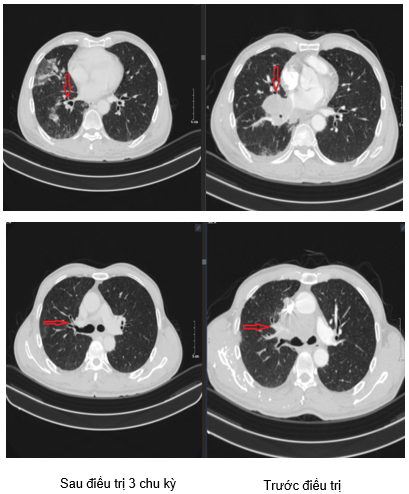

Hình 2. Hình ảnh tổn thương nhu mô thùy dưới phổi phải sát rãnh liên thùy: Sau 3 chu kỳ điều trị kích thước giảm xuống còn 28x18mm (hình bên trái) so với trước điều trị kích thước 45x36mm (hình bên phải).

Hình 3. Hình ảnh tổn thương thùy trên phổi trái: Sau 3 chu kỳ điều trị (hình bên trái) giảm kích thước so với trước điều trị (hình bên phải).